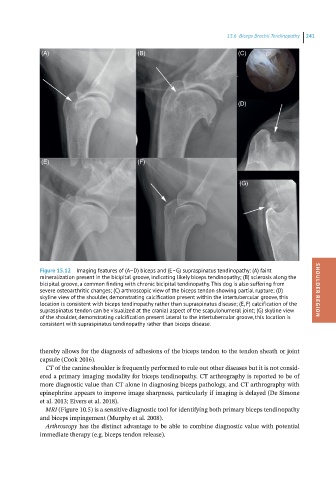

Figure 15.12 Imaging features of (A–D) biceps and (E–G) supraspinatus tendinopathy: (A) faint

mineralization present in the bicipital groove, indicating likely biceps tendinopathy; (B) sclerosis along the

bicipital groove, a common finding with chronic bicipital tendinopathy. This dog is also suffering from

severe osteoarthritic changes; (C) arthroscopic view of the biceps tendon showing partial rupture; (D) SHOULDER REGION

skyline view of the shoulder, demonstrating calcification present within the intertubercular groove, this

location is consistent with biceps tendinopathy rather than supraspinatus disease; (E, F) calcification of the

supraspinatus tendon can be visualized at the cranial aspect of the scapulohumeral joint; (G) skyline view

of the shoulder, demonstrating calcification present lateral to the intertubercular groove, this location is

consistent with supraspinatus tendinopathy rather than biceps disease.